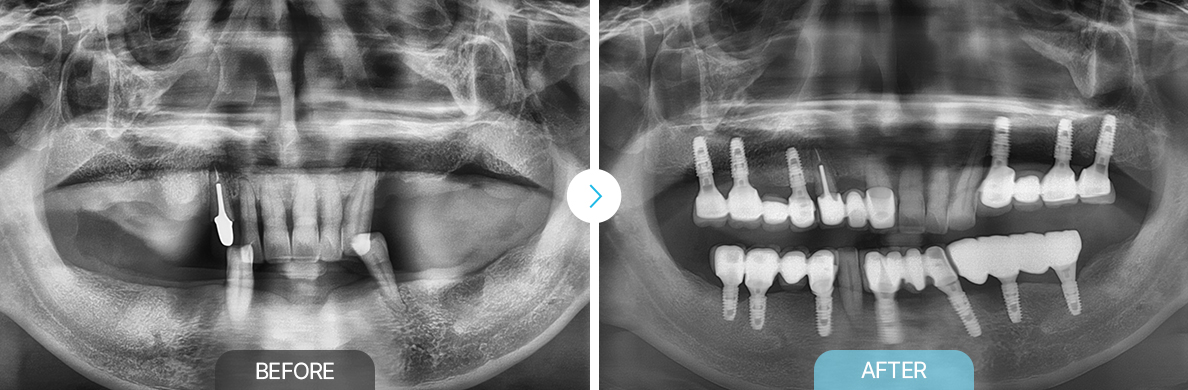

임플란트/틀니

BEFOREAFTERBEFOREAFTERBEFOREAFTERBEFOREAFTER